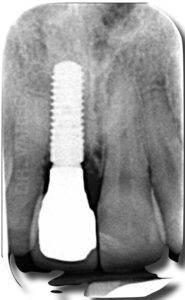

Il paziente dopo lo shock iniziale ritrova l’estetica e la sicurezza di sorridere di nuovo. L’immagine di colore grigio mostra come appare un impianto in radiografia.